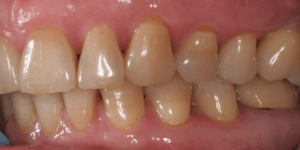

Для предварительной подготовки были привлечены пародонтолог и ортопед, поскольку отсутствие нескольких зубов, заболевание пародонта и дефекты твердых тканей зубов сопутствовали основной патологии. Проведены пародонтологические процедуры, вылечен кариес и его осложнения, изготовлены временные коронки для зубов с большим разрушением. На фото — временные коронки на боковых зубах.

Искривление окклюзионной кривой (плоскости смыкания зубов), возникшее в результате парадонтита, успешно удалось устранить, используя накусочные брекеты на верхних резцах и микроимплант, установленный во фронтальном участке нижней челюсти: